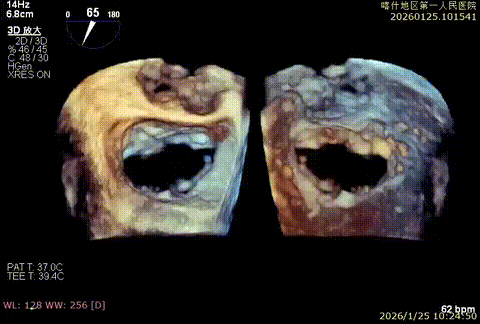

3D enface后叶栓系

3D enface观察反流

3D enface 观察脱垂

3D enface脱垂情况

该例患者为VFMR,术前制定手术策略:患者二尖瓣重度反流,后叶严重栓系,心房心室扩大。患者瓣口面积4.5cm2,预计使用两枚XTR解决患者瓣叶脱垂和反流。考虑到先于2区进行钳夹,应该能获得足够的房间隔穿刺高度。术中经不断调整穿刺位点,最终穿刺高度4.4cm。成功穿刺后将第一枚XTR送入二尖瓣正上方,进行弹道测试Orientation调整后,最终定位于2区正上方下左心室。第一枚夹子在左室成功捕捞和钳夹瓣叶后,瓣叶反流程度显著降低,夹子外侧仍见部分反流,随后在第一枚夹子外侧再次放置一枚XTR,瓣叶反流程度进一步降低至微量。通过TEE观察,二尖瓣双孔组织桥稳定,跨瓣压差3mmHg,肺静脉逆流改善明显,手术安全结束。

该例患者为DMR类Barlows患者,二尖瓣重度反流,患者1,2,3区均可见脱垂,脱垂主要源于3区,反流主要源于3区。术前制定手术策略:使用一把XTR解决患者瓣叶脱垂与二尖瓣反流。术中进行房间隔穿刺后将XTR-CDS送入左心房,通过操控“M”旋钮,成功将二尖瓣夹定位于2区正上方。在2区进行弹道测试成功后,进行Orientation调整。在3区将二尖瓣夹送入左心室,成功捕捞和夹持瓣叶后缓慢关紧夹臂,解决大部分反流,Saide by Saide L植入第二把XTR。TEE检查见二尖瓣反流程度充分降低至1+,二尖瓣双孔组织桥稳定,跨瓣压差3mmHg,肺静脉逆流改善明显,手术安全结束。